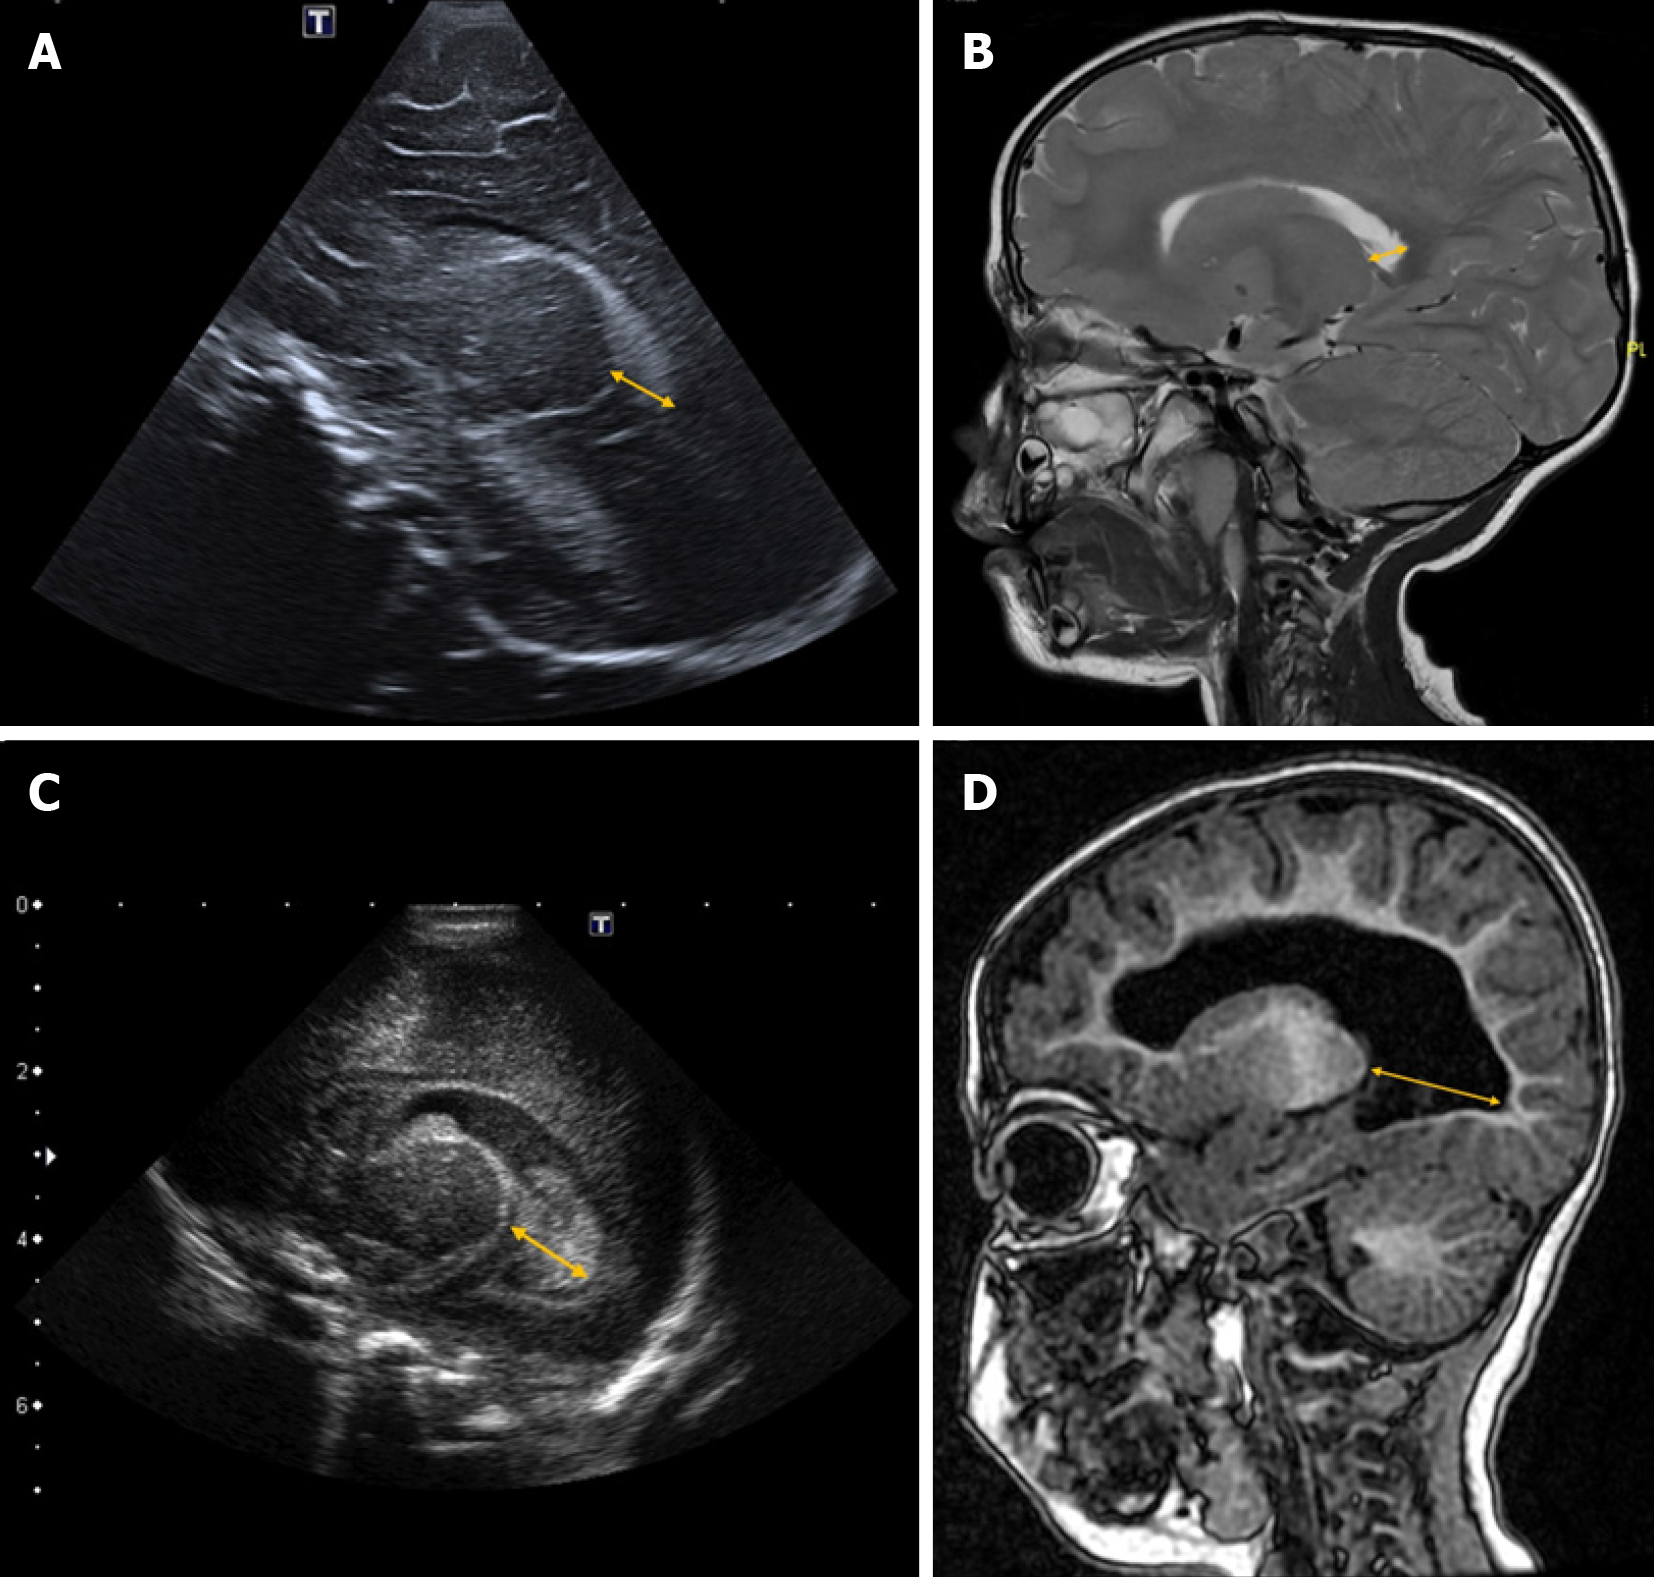

Levene’s index is a quantitative measure used to assess the size of the lateral ventricles in neonates, particularly during the first 40 weeks of gestational age[18]. It is calculated on a coronal plane at the level of the foramen of Monro by measuring the distance from the midline (falx cerebri) to the lateral wall of the anterior horn of the lateral ventricles on both sides (Figure 1)[3].

Reference values vary depending on gestational age. Some authors suggest that hydrocephalus treatment should be considered when this distance exceeds 4 mm above the 97th percentile[19,20]. However, it is essential to develop updated reference nomograms tailored to neonatal populations with shared phylogenetic characteristics to ensure standardized values for each group[3].

This index measures the distance between the posterior edge of the thalamus at its junction with the choroid plexus and the outermost point of the occipital horn of the lateral ventricle in the parasagittal plane[20] (Figure 2).

Although some authors consider a thalamo-occipital distance greater than 24 mm to be pathological[19,21], reference values can vary depending on the specific population and gestational age[22].